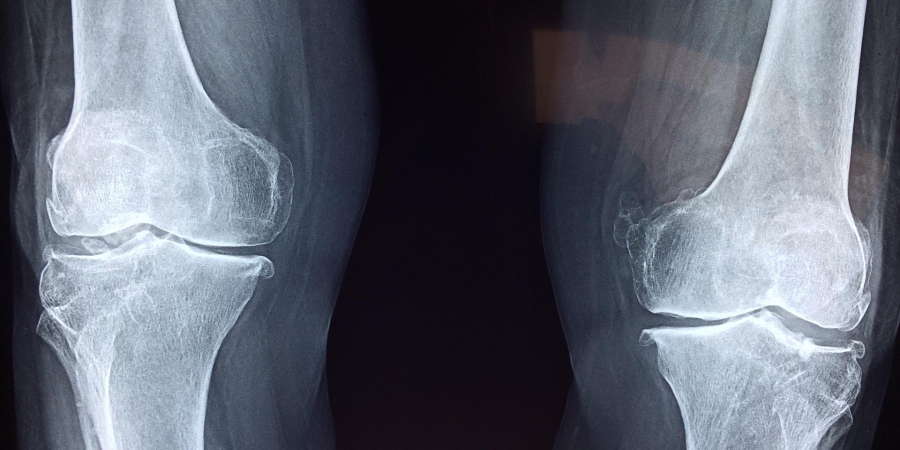

Stellenwert der Reha bei Knorpelverletzungen

Knorpeldefekte durch Sport sind eine ernste Sache. Univ.-Prof. Dr. Stefan Nehrer, Dekan der Fakultät für Gesundheit und Medizin der Donau-Universität Krems, stellte auf dem 37. GOTS Kongress in Berlin neben den gängigsten operativen Verfahren eine lange, gute und intensive Reha in den Fokus: Zur Reha bewegt nach der OP am Anfang eine Motorschiene das Gelenk passiv. In den ersten vier Wochen wird langsam eine Belastung aufgebaut.

Nach 5-6 Wochen kann das Gelenk erst voll belastet und stabilisierender Muskelaufbau forciert werden. Erst nach 12 Wochen kann wieder leichter Sport, am besten Radfahren, betrieben werden. Laufbelastungen sind erst nach 6 Monaten empfehlenswert, Fußball oder Ski alpin erst nach einem Jahr.